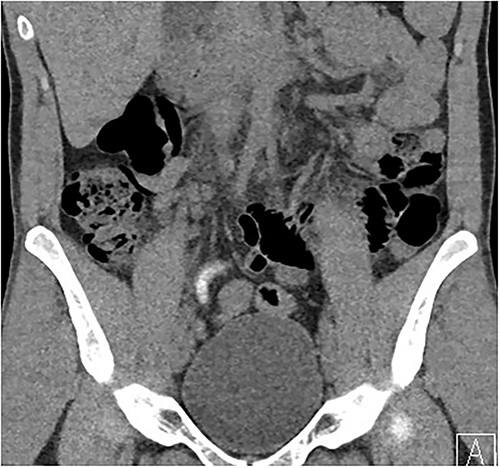

Two days following stent removal, the patient developed acute onset right lower quadrant and flank pain. A non-contrast CT of the renal tract was obtained to assess for procedure or stone-related complications. The scan demonstrated two distinct retained stones within the proximal right ureter, with associated moderate ureteronephrosis. Additionally, within the right lower quadrant of the abdomen, a radiopaque vermiform entity was demonstrated (Figs 1–3). This entity was not pathological, however, represented a normal appendix that had, consequent to contrast administration during a urological procedure, become filled with contrast secondary to vicarious contrast excretion.

Coronal imaging, demonstrating contrast-filled vermiform structure.